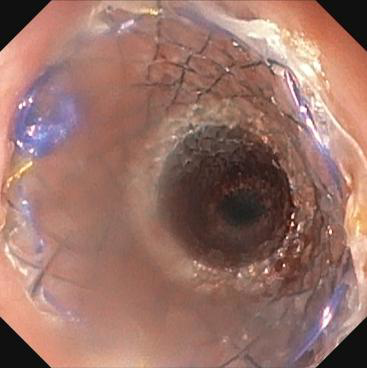

近日,pilipili 消化内科接诊了一位因胰胃间隙恶性肿瘤、食管狭窄,无法进食的91岁营养不良患者。患者入院后,在进行更换胃管时,发现普通胃管已无法通过,行胃镜检查中发现狭窄明显。经过院内专家团队的评估,决定采用超细胃镜尝试,并成功放置了空肠管。针对该患者高龄、身体虚弱、营养不良等实际情况,经与家属沟通,同意行内镜下放置食管支撑架。手术由陈东副主任医师和陈达主治医师完成,术后患者的食管狭窄得到缓解,可自主进食,生活质量得到了显著提升。

首选覆膜自膨式金属支架。ESGE 在食管支架置入术指南中,建议置入一个完全或部分覆膜的自膨式金属支架(fcSEMS/pcSEMS) 用于治疗恶性吞咽困难,有研究表明其移位率更低。在支架长度的选择上,根据食管肿瘤位置、长度和食管直径选择合适的食管支架,通常支架至少比病变长度长3-4 cm,使支架置入食管后支架远端超过狭窄段15-20 mm,近端高出病变20mm 左右,确保支架覆盖整个病变范围,但对于肿瘤邻近主动脉弓者,食管支架近端应超出主动脉弓上缘,以避免随着主动脉搏动,支架上极机械摩擦导致食管穿孔,甚至主动脉穿孔大出血。